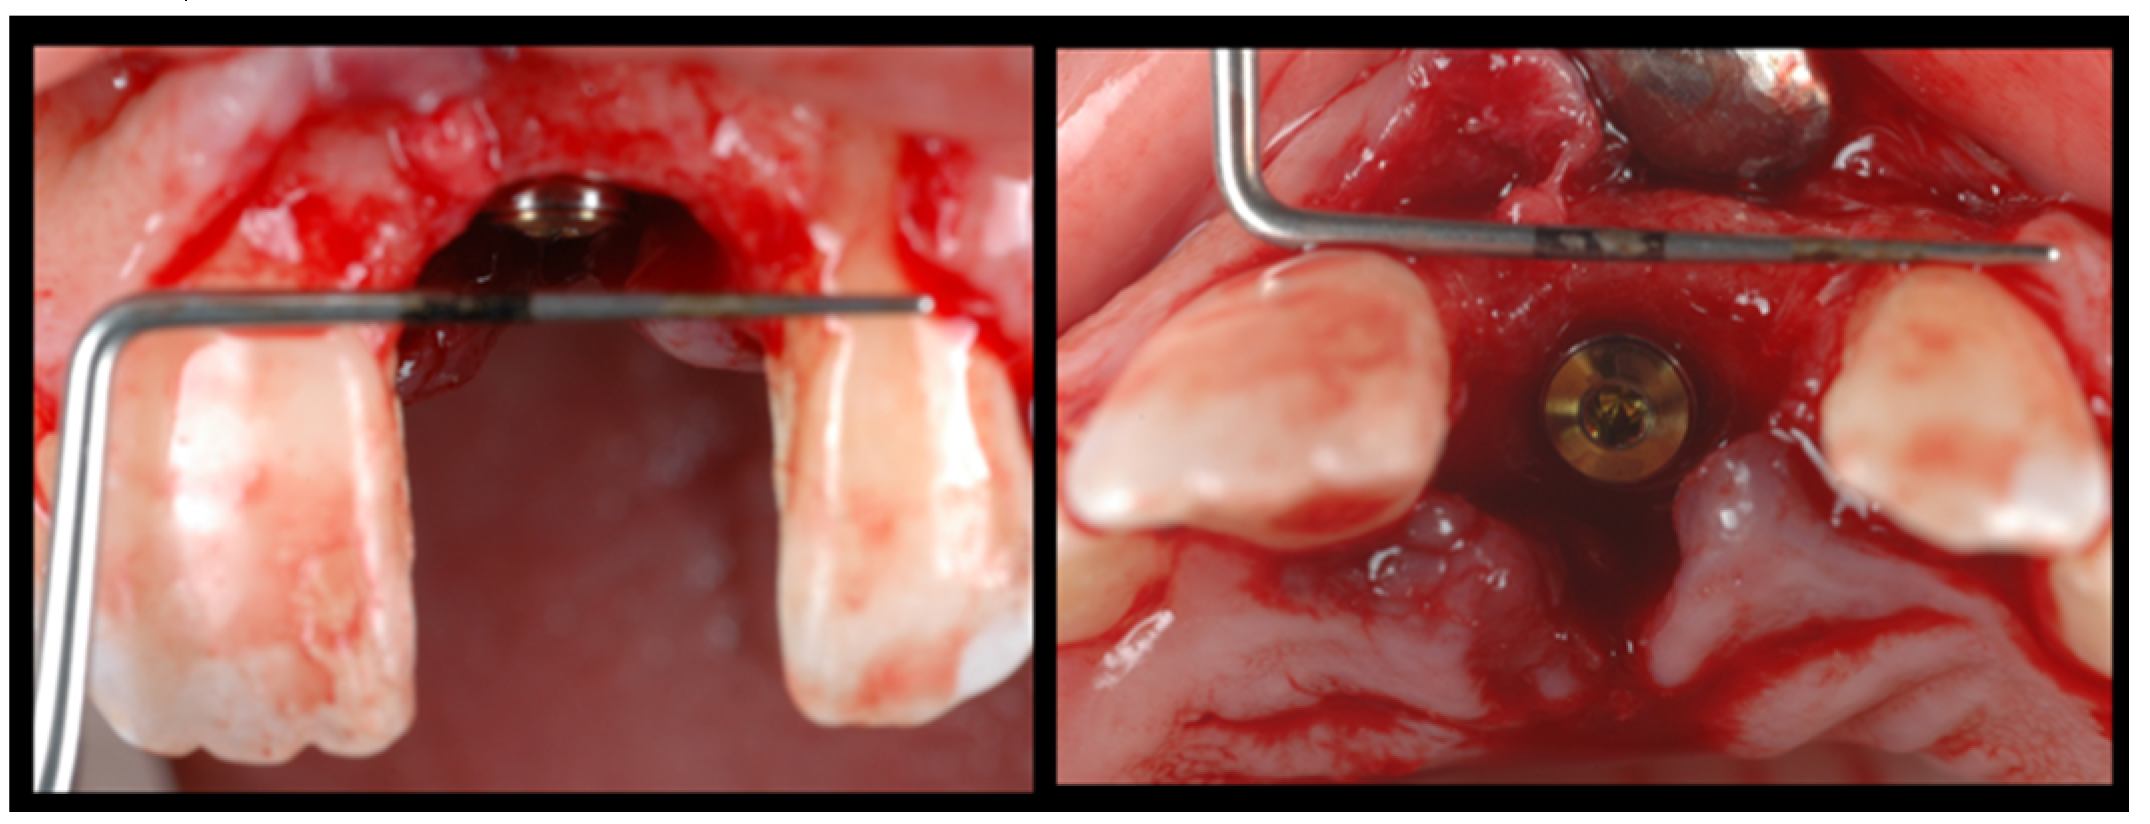

During the second surgery, 6 to 10 months thereafter, the fixation screws were removed. With the help of a surgical guide, Tapered Internal Laser-Lok® 3.8 implants with a 3.5 mm prosthetic platform (BioHorizons, Birmingham, AL, USA) were positioned in the correct 3D position. Provisional restoration consisted of an acrylic crown attached to the teeth adjacent to the gap with an adhesive system (Figure 5).

Figure 5.

With the help of a surgical guide, implants were positioned in the correct 3D position.